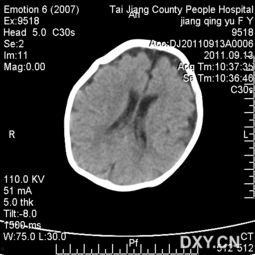

首先,让我们来了解一下什么是成人头颅未闭合。这其实是一种医学上的罕见现象,叫做颅缝闭合不全。简单来说,就是人的头骨在发育过程中,颅缝没有完全闭合。这种情况在婴儿和儿童中较为常见,但在成年人中却极为罕见。

例如,YouTube上有一个名为“医学奇迹”的频道,就曾发布过一段成人头颅未闭合的视频。视频中,我们可以清晰地看到,这位成年人的头骨上有一个明显的缝隙,而且这个缝隙并不是由外伤造成的。